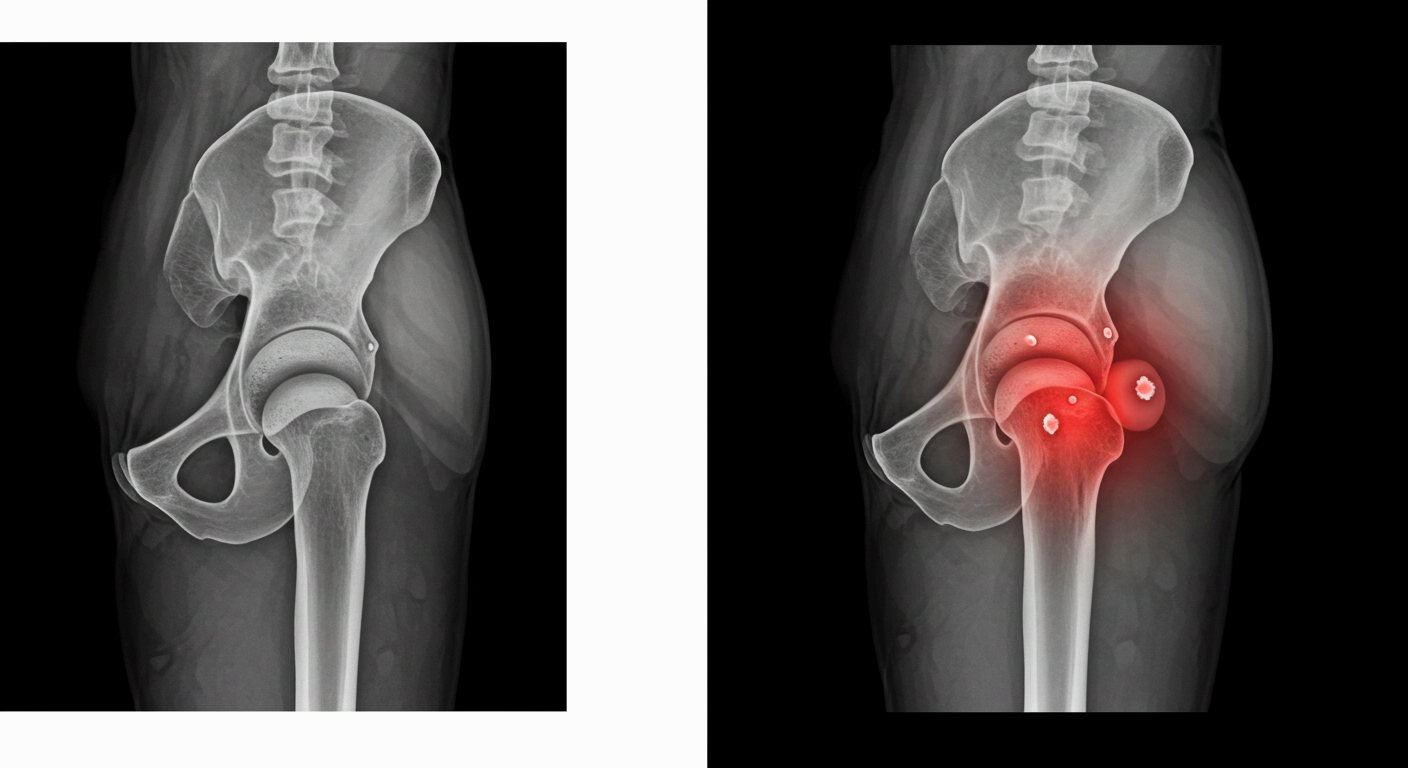

고관절 통증 증상, 이렇게 나타납니다

고관절 통증은 단순히 엉덩이 부위만 아픈 것이 아니라, 사타구니·허벅지·엉덩이·무릎 등 여러 부위로 연관 통증이 나타나는 복합 증상입니다.

특히 걷거나 앉는 일상적인 행동 중 불편함을 느낀다면, 이미 고관절 이상이 시작된 것일 수 있습니다.

고관절 통증 원인, 왜 아픈 걸까요?

고관절은 골반과 허벅지를 연결하는 관절로, 걷기, 앉기, 뛰기 등 거의 모든 움직임에 관여합니다.

📌 고관절 충돌 증후군 (FAI)

- 대퇴골두와 비구가 부딪히는 구조적 이상으로 통증 유발

- 주로 젊은 운동선수나 활동량이 많은 사람에게 발생

📌 퇴행성 고관절염

- 고관절 연골이 닳아 없어지며 뼈와 뼈가 직접 마찰됨

- 50대 이상에서 흔하며, 통증·운동 제한·관절 소리 등이 특징

📌 대퇴골두 무혈성 괴사

- 혈액 공급 부족으로 뼈 조직이 괴사되어 통증 유발

- 음주, 스테로이드 과다 사용 등도 원인이 될 수 있음